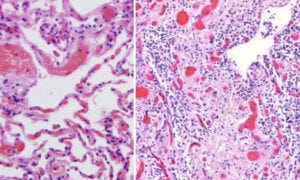

11. Healthy heart muscle tissue, and lymphocytic myocarditis

In Slide 7, we saw that heart muscle cells strongly expressed the spike protein after vaccine injection. Here, we see the consequences. The picture on the shows a sample of healthy heart muscle tissue, with regularly oriented and aligned heart muscle fibres. On the right, we see a heart muscle sample from one of the autopsies. The muscle fibres are disjointed and disintegrating, and they are surrounded by invading lymphocytes. Burkhardt found myocarditis in multiple of his deceased patients.

12. Lymphocytic infiltration and proliferative inflammation in lung tissue

On the left, we see healthy lung tissue, with air-filled spaces (the alveoli), delimited by delicate alveolar septa with embedded, blood-filled capillaries. We also see some larger blood vessels.

On the right hand side, we see lung tissue overrun by lymphocytes. The air-filled spaces have largely disappeared and been filled with scar (connective) tissue. This vaccine-injected patient would obviously have had very great trouble breathing.

Lymphocytic infiltration, inflammation and destruction were also observed in many other organs, including the brain, the liver, the spleen, and multiple glands. However, instead of illustrating them all, we will conclude the pathological evidence with another immunohistochemistry result, which strikingly shows the long duration of spike protein expression.